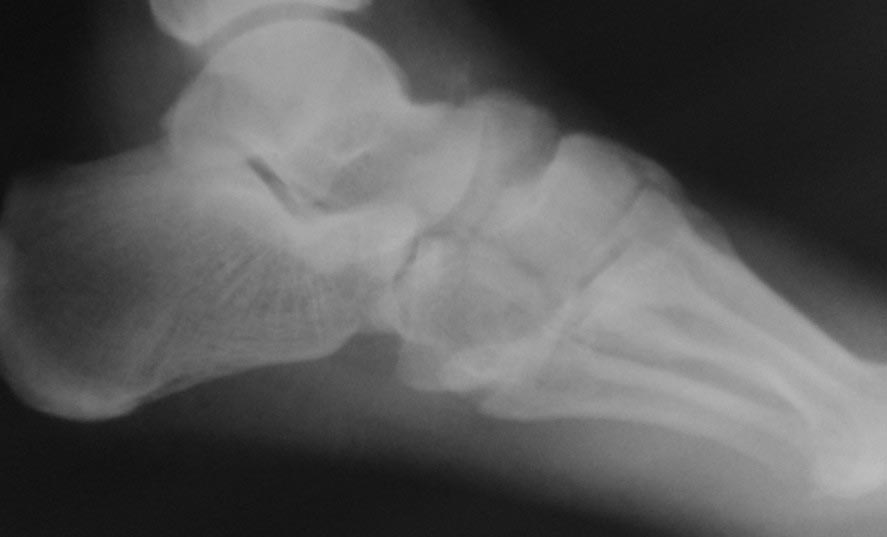

[Ortho] застарелый переломовывих в суставе Шопара

Обратился пациент 40 лет через 2,5 мес после травмы,

не курит, социален. Первым этапом наложили дистрактор, дозированная

дистракция, вторым этапом планировали репозицию ладьи с bridge plate

(шейка - клин). После выходных обнаружили такую картинку некрозов,

доступ планировался именно так. Считаю, что основная проблема в

ладье. Фрагмент ладьи абс неподвижен. Вопросы: стоит рисковать или нет?

будет ли менее рискованная операция позже по рубцу? Что еще следует

учесть (возможно недопонимаю анатомию повреждения)? Другие варианты?